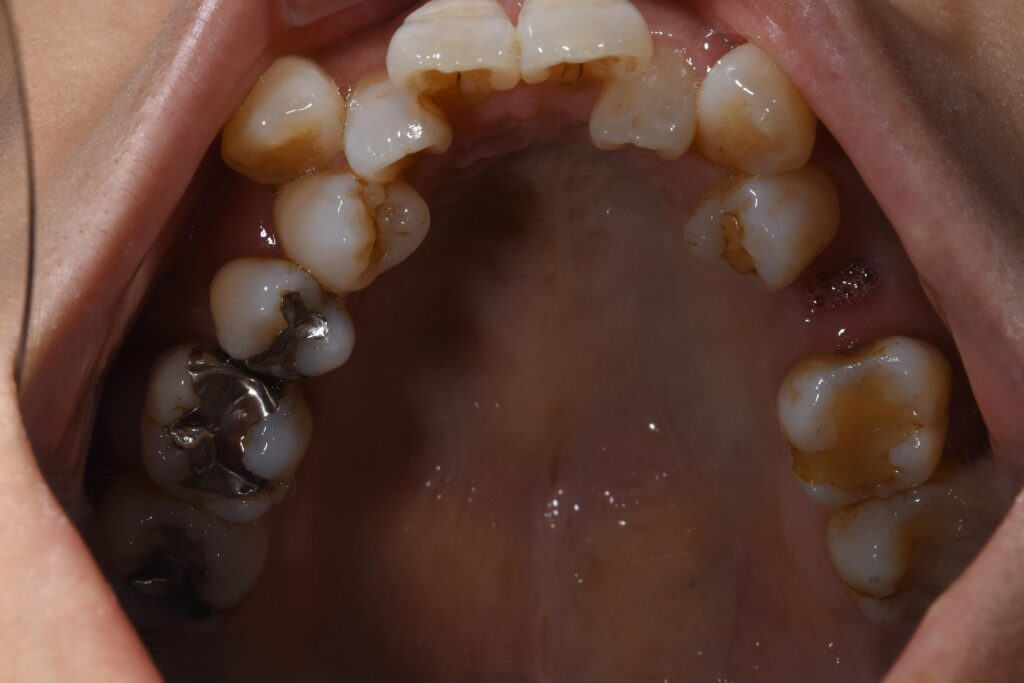

まずは矯正開始前の状態です。

写真が暗くて申し訳ございません。

【矯正開始前】

この患者様の問題点を以下に列挙します。

【問題点】

①歯のががたつきが強く、清掃困難な状態である。

②かみ合わせに問題があり、左上5番目の歯が歯周病で保存困難となったため、抜歯が必要となった。

③歯を並べるスペースが窮屈であり、スペース獲得のため便宜的な抜歯治療が必要である。

大まかに上記3点となります。

今回のように、下の歯のがたつきが顕著な場合、インビザライン(マウスピース)のみで歯並びを改善するよりも、針金を併用する治療も治療計画として考えましたが、患者様ご希望にて、針金は一切使用せず、インビザラインのみで矯正治療を行うこことなりました。